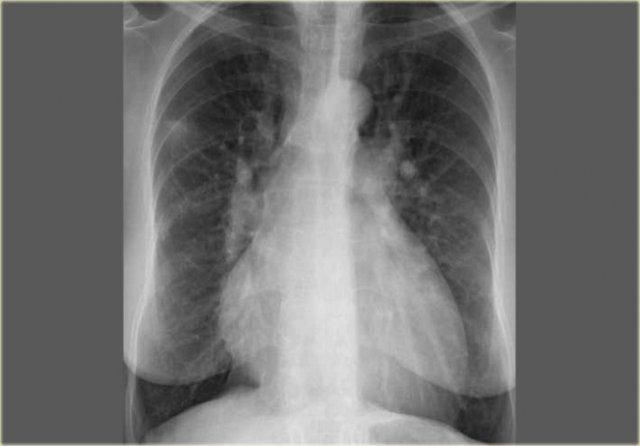

On the left a chest film of a young adult with a cough.

There is a right paratracheal mass.

The differential diagnosis is tumor, adenopathy or vessel (right arch, dilated azygos vein, dilated aberrant right subclavian artery).